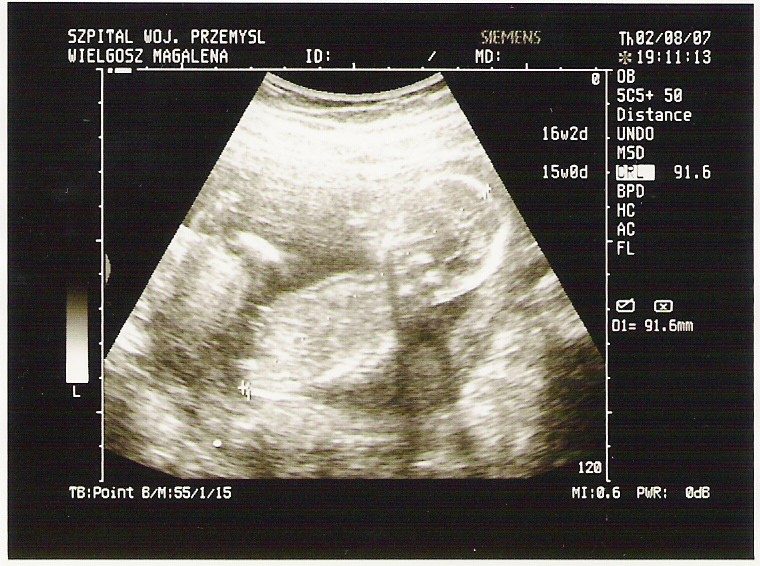

Witam chciałam sie przedstawić. mam termin w styczniu, to moje 1 dziecko, chyba dziewczynka, bo ptaszka nie widac, a już 5 miesiac sie zaczyna

Na poczatku ciazy miałam troche problemów, jakis krwiak ( ale bez krwawień), brałam luteinę, jakies infekcje ucha, gardła i tysiace rzeczy, ale teraz jest juz ok, łozysko sie ukształtowało i nie przoduje, wynini badań idealne... ufff

kolejna wizyta 29-08 może coś wyjaśni - zobaczymy